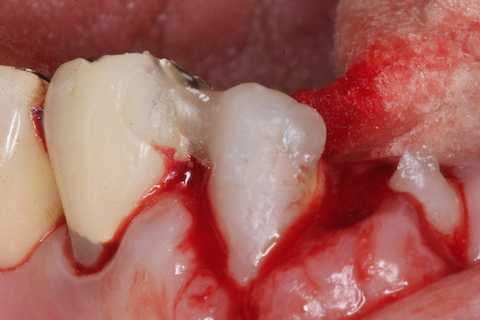

普通にズブズブと抜歯窩に再建した歯根を挿入する。

あとは接着固定しながら、歯冠を再建していく。